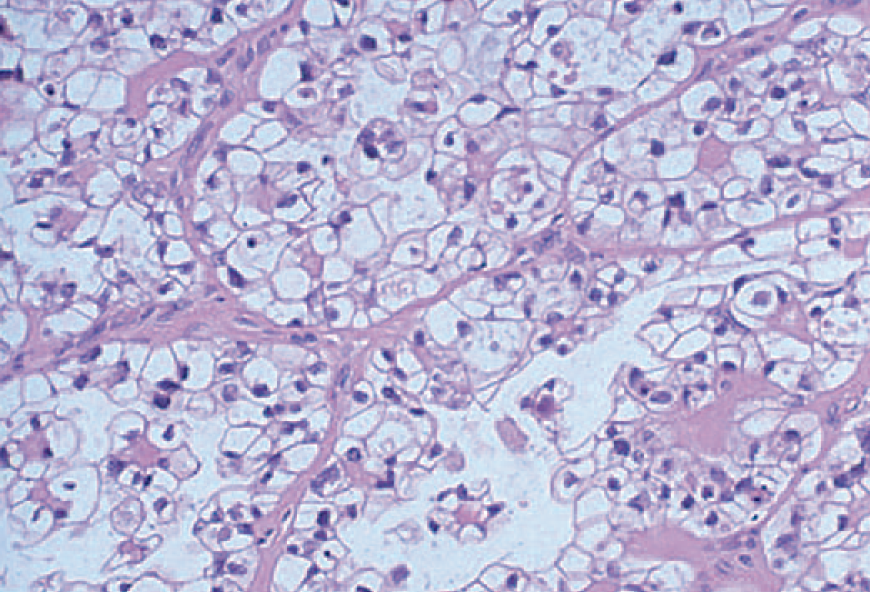

Clear cell vaginal carcinoma, think someone whos mom was given DES while in utero